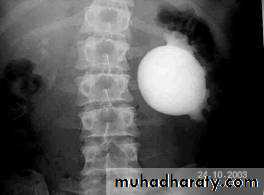

Pelvi-ureteric junction obstructionFilling defects

Multiple Calculi in the Renal Pelvis. A retrograde pyelogram demonstrates multiple filling defects